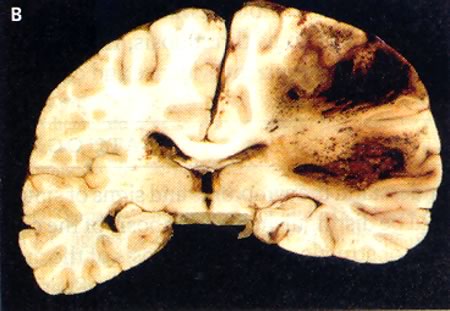

Figura

3 – Aspetto post-mortem della trombosi dei seni (Stam J, 2005)

La

figura 3 mostra un vasto infarto venoso emorragico nel cervello dello

stesso paziente.